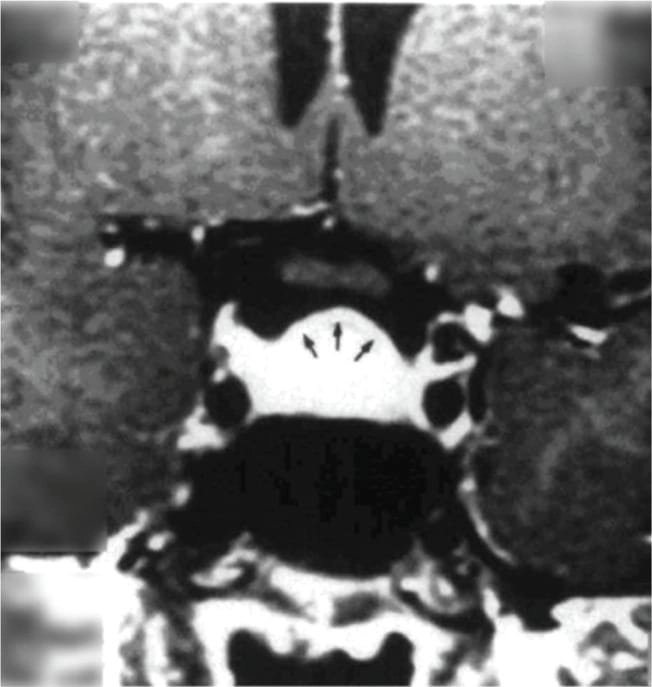

তবে পিটুইটারি হাইপারপ্লাসিয়া দেখা যায় প্রাইমারি গনাডাল, অ্যাডরিনাল বা হাইপোথাইরয়েডিজমের মত এন্ড অর্গান ইনসাফিসিয়েন্সিতে। বিশেষ করে, অব্যবহৃত প্রাইমারি হাইপোথাইরয়েডিজমে পিটুইটারি হাইপারপ্লাসিয়া পূর্বের ধারণার তুলনায় অনেক বেশি দেখা যায়। ২০১৯ সাল পর্যন্ত এরকম ১০৫টি কেস রিপোর্ট করা হয়েছে। এই ধরনের হাইপারপ্লাসিয়া গম্বুজ-আকৃতির (dome-shaped) হয়ে অপটিক কায়াজমাকে চেপে ধরতে পারে, যার ফলে অপারেশনের প্রয়োজন পড়তে পারে—যেমনটা আমাদের তৃতীয় কেসে ঘটেছিল।

কেস ২: একই রকমভাবে, ১৫ বছর বয়সী আরও একজন কিশোরী অল্প উচ্চতা ও টিউমার সন্দেহে নিউরোসার্জেনের কাছে রেফার করা হয়। তার TSH ছিল 100 এবং MRI-তে একটি ডোম-আকৃতির টিউমার দেখা যায়। যাকে ওষুধের চিকিৎসায় সত্য জীবনে ফিরিয়ে আনা হয় এবং ৬ মাসে তার উচ্চতা বৃদ্ধি পায় ও নিয়মিত মাসিক শুরু হয়। MRI-তে টিউমার সম্পূর্ণ অদৃশ্য হয়ে যায়।

চিকিৎসক তথা আবিষ্কারক সত্যম তিনটি কেসের বিষয় নিয়ে যখন তুলনা করতে নিলেন এবং পুরনো সৃষ্টি ঘাটতে শুরু করলেন তখন তিনি দেখতে পান সবগুলি ক্ষেত্রেই একই রকম সাদৃশ্য অর্থাৎ পিটুইটারি গ্রন্থি মাঝের অংশ এই গ্রন্থি দেখতে খানিকটা প্রজাপতির মতোই এবং তার মাঝের অংশের (প্রজাপতির দেহের উপরের অংশ মাথার মতই দেখতে) উপরের ভাগ সব ক্ষেত্রেই ডোমের মত বা গম্বুজ আকৃতির। তিনি এই ডোম বা গম্বুজ আকৃতি হওয়ার কারণ বিশ্লেষণ করতে গিয়ে দেখেন পিটুইটারির সামনের অংশ যেখানে থাইরোট্রপগুলো থাকে, যেখান থেকে এই টিউমারটি হয়। আর যখনই এটি বাড়বে তখন টমের মতনই তৈরি হবে। অর্থাৎ গম্বুজ আকৃতির। আর সেখান থেকেই ডোম-সাইনের উৎস অর্থাৎ আবিষ্কার।

MRI-তে এই হাইপারপ্লাসিয়া সাধারণত গম্বুজ-আকৃতির ও সমমিত হয় এবং হোমোজেনাস সিগনাল ইন্টেনসিটি দেখায়, যেখানে সাধারণ নন-ফাংশনাল পিটুইটারি অ্যাডেনোমা নানা আকার ও অসমতা নিয়ে দেখা যায়।

তাঁর দাবি, MRI-তে ‘DOME Sign’ থাকা এবং TSH বাড়তি থাকলে, সেটি হাইপোথাইরয়েডিজম-জনিত হাইপারপ্লাসিয়ার সম্ভাবনার কথা নির্দেশ করে এবং এই রোগীদের শুধুমাত্র লেভোথাইরক্সিন দিয়ে চিকিৎসা করলে পূর্ণ আরোগ্য সম্ভব।